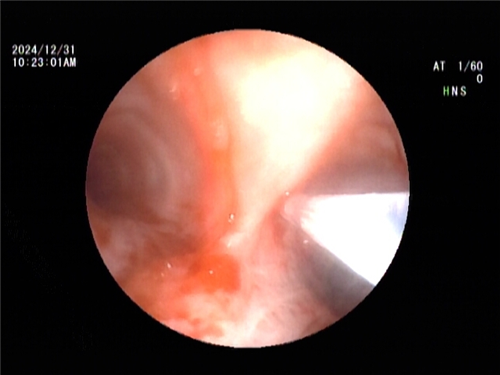

随后,王海龙主任带领呼吸内镜介入团队,为患者实施了支气管镜引导纵隔淋巴结活检(TBNA)。手术过程顺利,获取了满意的组织标本。经病理检查提示:(隆突下淋巴结)为非坏死上皮样肉芽肿性病变伴多核巨细胞反应。